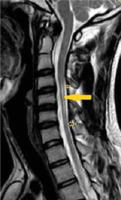

Figure 7

Sagittal T2W image in the flexion position in a patient showing anterior displacement of the posterior dura (white arrows). The flow voids are also seen in the posterior epidural space

Posterior epidural flow voids were seen in 13 patients on T2W images on flexion MRI (76.4%) (Figure 7). Almost all the patients (16 out of 17) showed thick crescentic-shaped homogenous intense enhancement in the posterior epidural space in the flexion position (Figure 10). The imaging findings are summarized in Table 2.

Flexion MRI shows the LOA, cord atrophy, and posterior epidural enhancement very well. On flexion MRI, all our patients showed forward displacement of the posterior dura, which is considered a hallmark of HD. This LOA of the posterior dura has been reported in various previous studies [5,18,21-24]. A study by Lehman et al. reported 100% specificity for the same, but with a lower sensitivity and false negative rates of LOA in a few patients [18]. These patients had a higher mean age (37.8 years), and it is believed that the findings of HD decrease with advancing age [1,15,18]. This forward displacement in the patients, measured as laminodural space (LDS) distance as stated by Boruah et al., can range from 3 to 9.8 mm, with a mean distance of approximately 5.99 mm [22]. However, our study showed this distance to be approx. 3.7 ± 0.66 mm (mean ± 2SD). This is lower than the distance measured in the study done by Boruah et al., which could be due to the larger number of patients included in their study. The most common site for maximum forward displacement of the dura in our study was at C6, seen in 58.8% of patients. The centre of displacement was also reported to be the C6 vertebra in the studies done by Hirayama et al. and Yin et al. [1,25]. On reviewing the axial sections for dural detachment from the adjacent lamina on flexion MRI in our patients, it was found to be bilateral in 13 patients (76.4%) and unilateral in 4 patients (23.5%). On searching the literature, we could not find any study on the evaluation of this imaging attribute in HD.

In another study done on HD, it was seen that the displacement of the posterior dura was also present in 46% of the normal population (controls); however, the extent of forward displacement was significantly less in them (0.99 ± 0.97 mm) compared to patients with HD (6.7 ± 0.78 mm). This forward displacement in controls was probably compensated by a corresponding increase in spinal canal volume, thus sparing the cord from compression [26]. However, the forward displacement in controls has not been reported by other studies [1,18,25]. Further research is required to study this imaging parameter in healthy subjects.

Crescentic homogenous enhancement was seen in the posterior epidural space on post-contrast flexion T1W images in almost all (93.7%) of the patients, which is in accordance with various studies [5,18,23]. Only one patient did not show enhancement: a follow-up case of HD aged 46 years. This can be explained by the fact that the findings of HD decrease with chronicity of the disease [1]. The enhancement has been attributed to the congestion of the posterior internal vertebral venous plexus [3]. There are 3 theories explaining the engorgement of venous plexus: 1) an anterior shift of the dura results in negative pressure in the posterior spinal canal, with resultant increased flow to the posterior internal vertebral venous plexus [6]; 2) the anterior internal vertebral venous plexus is compressed due to an anterior shift of the dura with resultant dilatation of the posterior internal vertebral venous plexus [5]; and 3) the venous drainage of the jugular veins is reduced in neck flexion, which compresses the venous return of the internal venous plexus [6]. Flow voids were seen in 76.4% of patients in the posterior epidural space on T2W images, which is in concordance with previous studies [10,11,13,22]. The aforementioned findings of forward displacement of the posterior dura, crescentic homogenous enhancement, and flow voids in the epidural space on flexion MRI are diagnostic of HD.